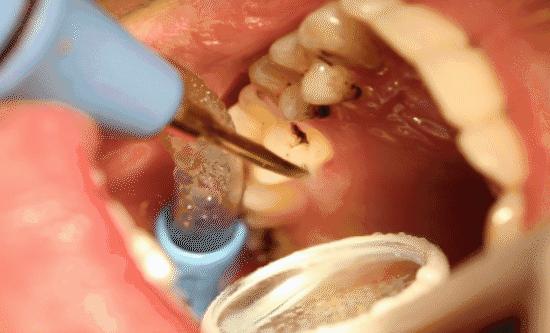

牙周炎的治疗方式之一

每半年至一年进行一次超声洗牙

洗牙能高效清除菌斑牙结石,维持牙龈健康,将牙周炎的始动因素消灭于萌芽状态。